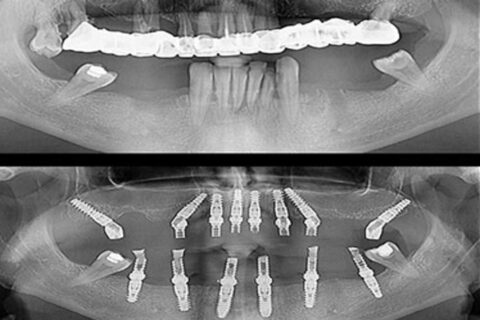

Zygomatic implants, also known as Zygoma implants, are an alternative to bone grafting techniques for the upper jaw and offer a viable option for individuals who desire dental implants but are severely deficient in upper jaw bone. These implants are inserted into the zygomatic bone (cheekbone) to support dentures, bridges, and upper jaw (maxillary) teeth, in contrast to traditional “root form” dental implants that are implanted into the jaws to replace teeth.

They pass transversely through the weak area of the upper jaw and attach to the bottom of the cheekbones via your sinuses.